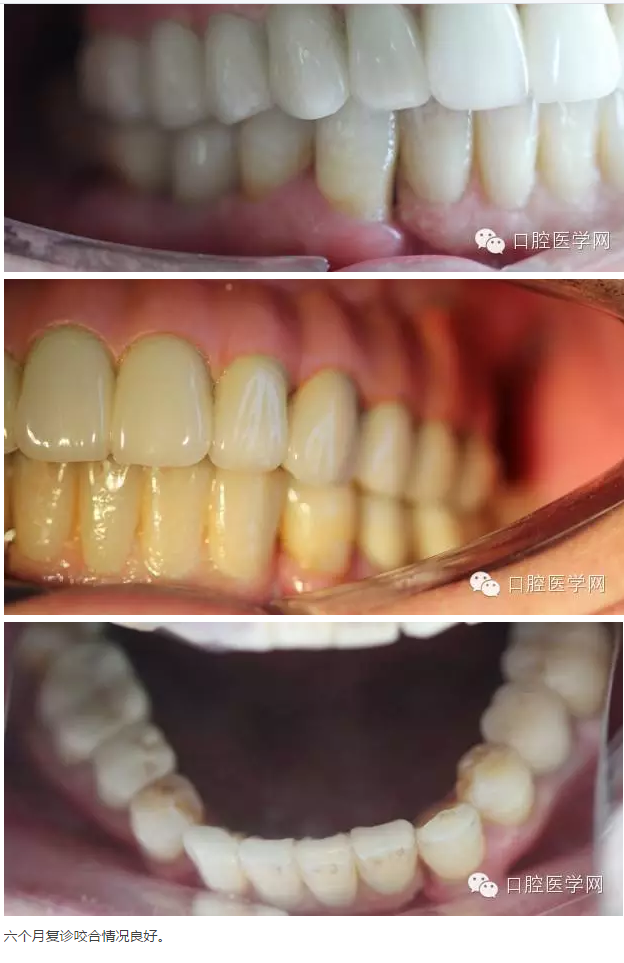

上頜牙全拔除進(jìn)行上頜ALL-ON- 6導(dǎo)航手術(shù)即刻種植即刻負(fù)重骨支持式導(dǎo)板,我們的要求為扭力大于等于35N ISQ值大于等于70直徑大于等于4長度大于等于11.5 數(shù)量大于等于4。

下頜32到42 區(qū)域擇期進(jìn)行即刻種植,植入三顆種植體后,常規(guī)活動臨時修復(fù)。

下頜45位置即刻種植不需要臨時修復(fù)。